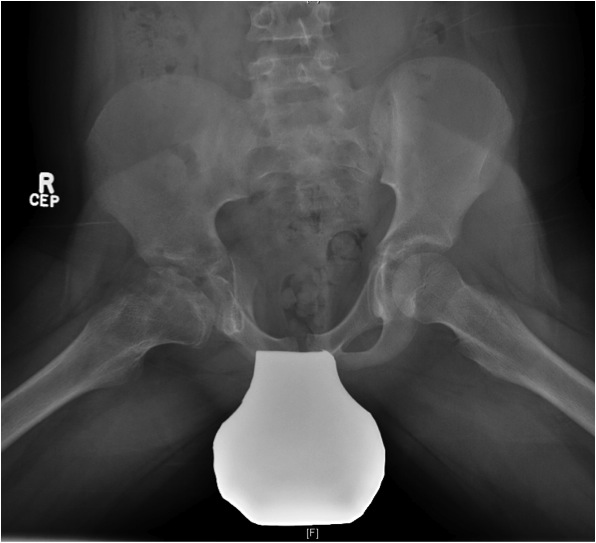

2. Resorption / fragmentation

Duration : 6/12

Pathologic Process

- necrotic bone irregularly resorbed / creeping substitution

- replaced with vascular fibrous tissue

- may be associated with collapse

XRay - Fragmentation of Physis

Herring Lateral Pillar

AP xray when disease in fragmentation / divide femoral head into 3 pillars

- lateral (25%)

- medial (25%)

- central (50%)